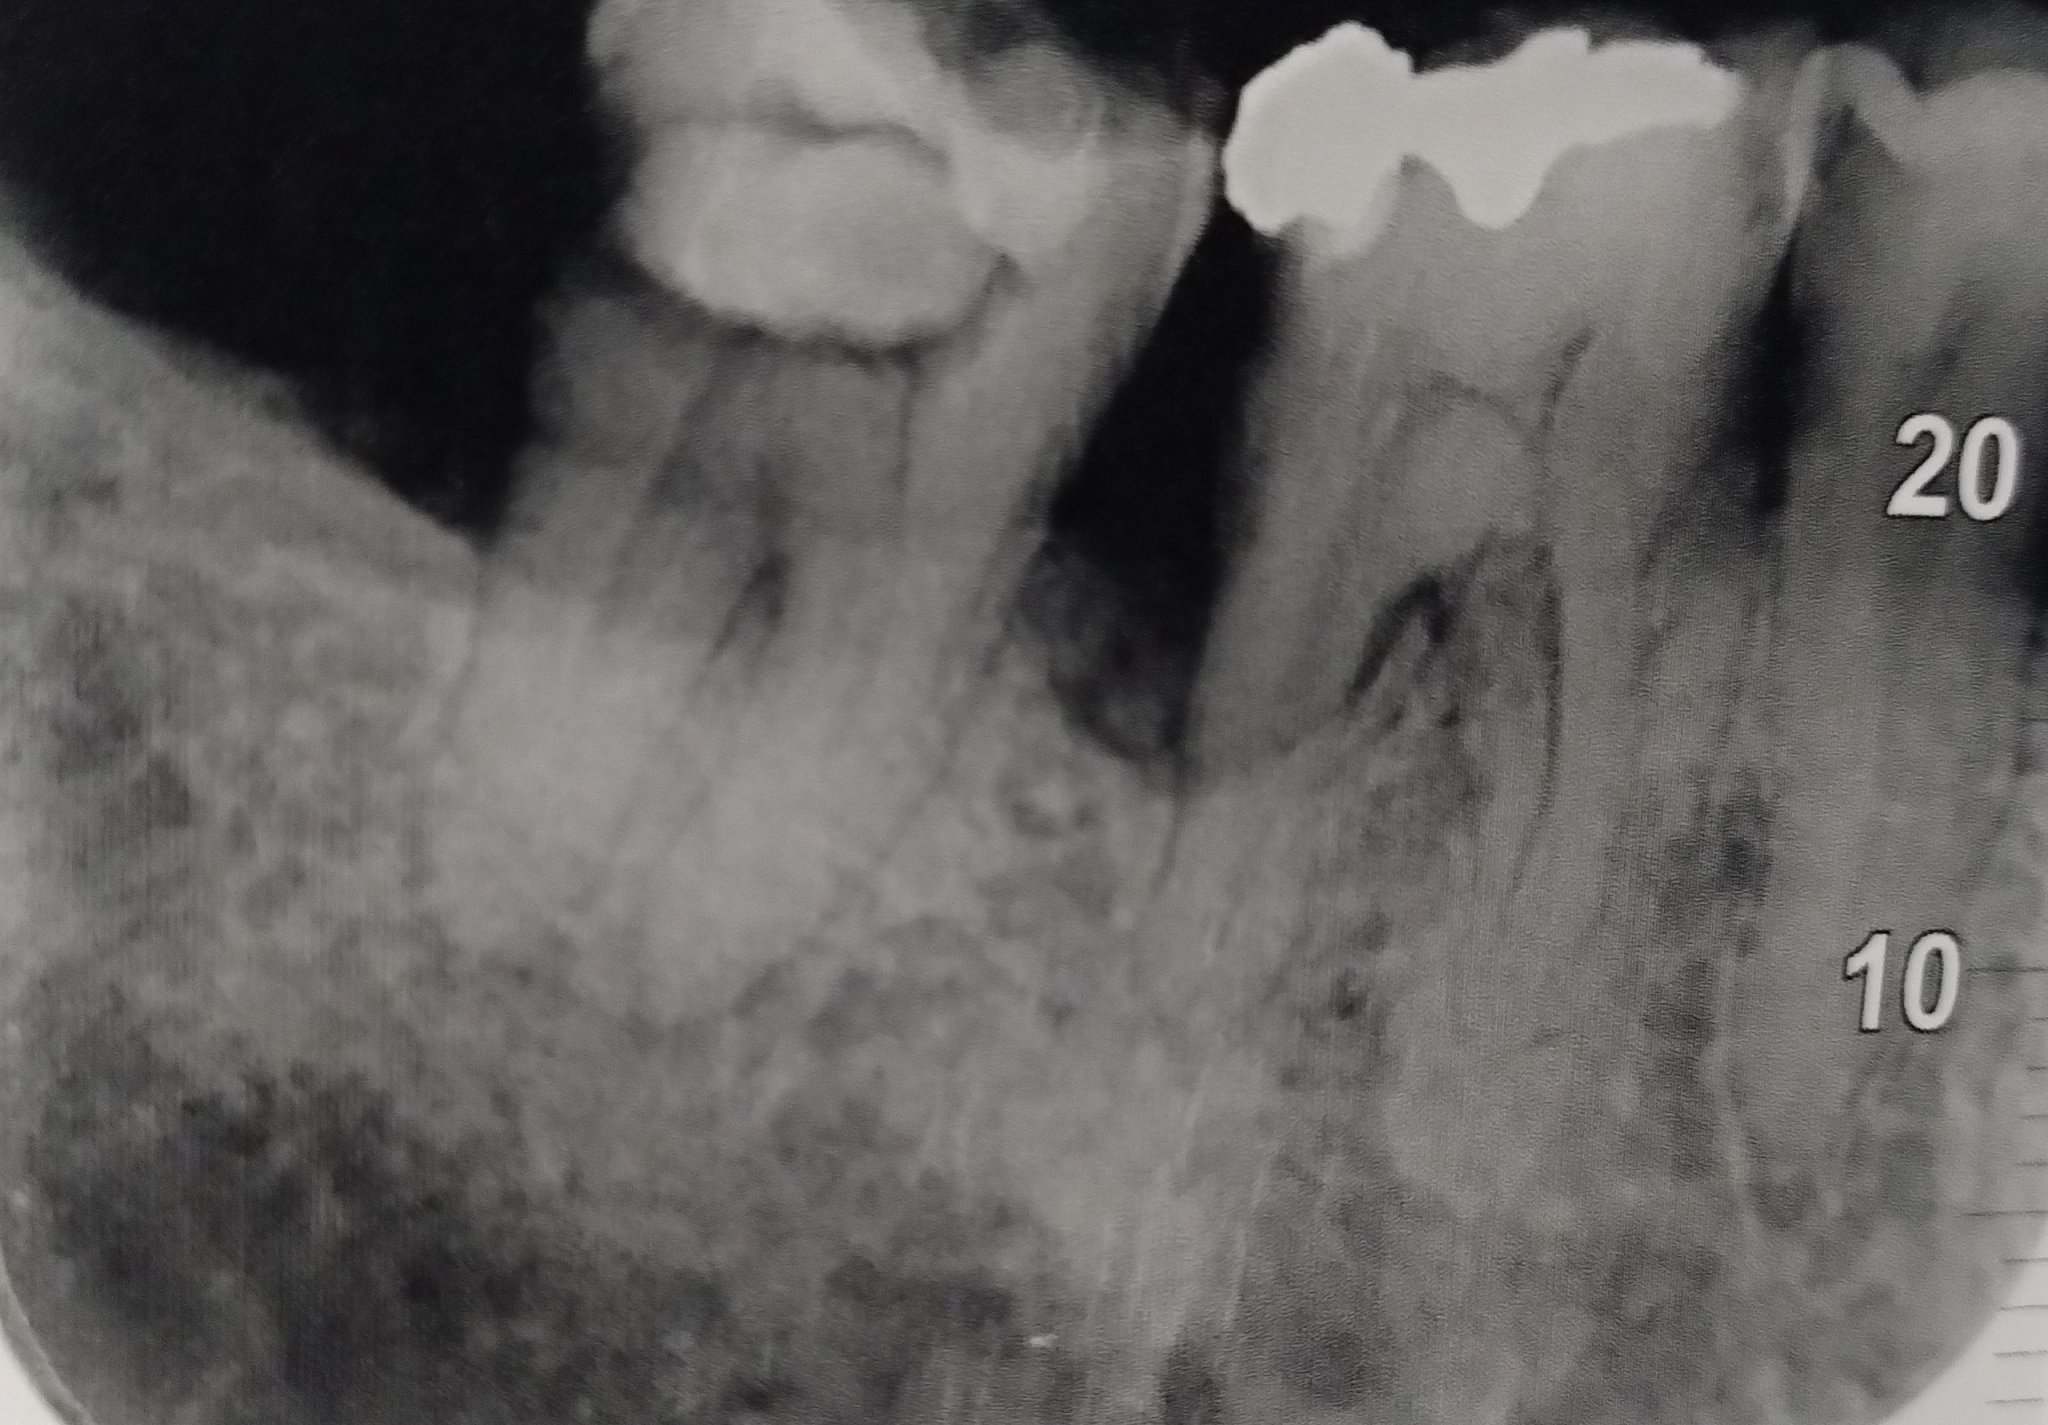

Регистрирах се специално, ако някой може да даде някаква насока, проблема е , лекувам кътник с пулпит, зъболекарката ми е е стара и много опитна, при нея се лекувам от както се помня и никога не съм имал проблем, зъбът ме заболя слабо преди месец

(краен кътник), болката отиваше към ухото, жената го отвори отстрани и отгоре, умъртви нервите, слага няколко пъти лекарство, извади ги с едни иглички ( каза че са два канала) и пак сложи лекарство, каза че антибиотик. Това в рамките на 3 седмици вече. През цялото това време, въпреки че нервите са извадени, болката се появяваше спорадично. Понякога не ме боли по цял ден и започне на другия сутринта да кажем, но никога не е спирала за повече от 2 дена. Болката не е остра, силна или непоносима, но си е обсебваща, тъпа и не би трябвало да я има. Жената каза че няма да слагаме пломба и пак почисти зъба и сложи временно лекарство, но нещата се запазват в същия вид. Отвори дори един друг зъб, за който имаше съмнение  вчера и на него му сложи лекарство, но не е от него, пак си ме поболва. Иначе никаква болка нямам при натиск, тя почукваше зъбите и ме питаше, никаква болка нямам при ядене, ям само на страната на този зъм нарочно и нямам болка, болката е след това и я усещам по скоро като към ухото. Но си е крайния зъб. Жената каза че няма логика, и каза че зъбът е здрав, понеже исках да го извадя че ми писна вече. Прилагам снимка на трите зъба, крайния лекувахме, тя каза че на снимката не вижда нищо , ако някой компетентен види нещо, нека пише за да знам дали да го лекувам или да го вадя че ми омръзна вече месец с тоя зъб да се занимавам

Костта е много стопена там.